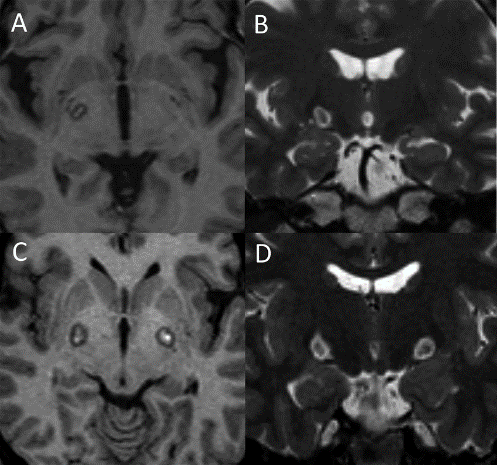

Stereotactic imaging maps the exact area in the globus pallidus that requires treatment.